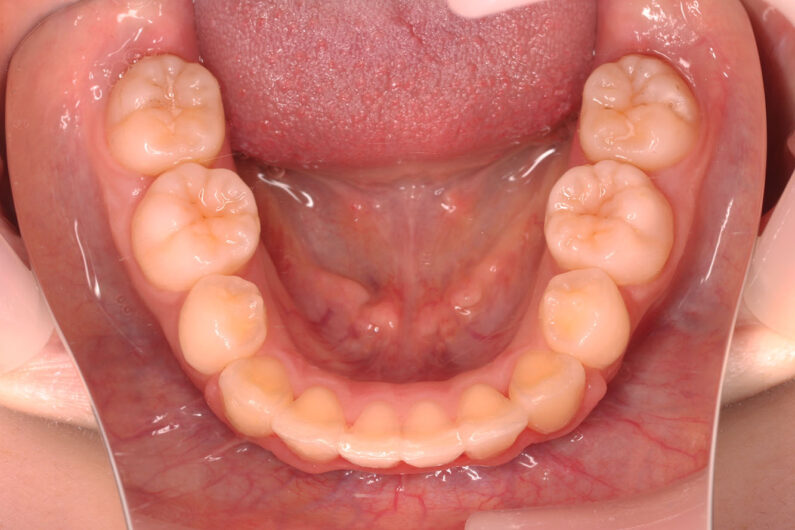

他院から紹介の患者さんです。 前歯、下の歯のガタツキをきれいにしたいということで治療を決断されました。

上顎前歯6mm、下顎前歯2.5mmの前突の状態で、口唇も前突しています。 小臼歯抜歯したスペースを使い、叢生(がたつき)と前突した前歯の後退を目標にしました。 この方も希望により、アンカースクリューは使用せず、通常の顎間ゴムで対処してもらいました。

マルチブラケット 動的治療期間 3年5か月 調整回数29回

治療後は前歯は後退し、前歯の傾斜度も良くなっています。 口唇の緊張感も改善し、エステティックラインも綺麗になりました。